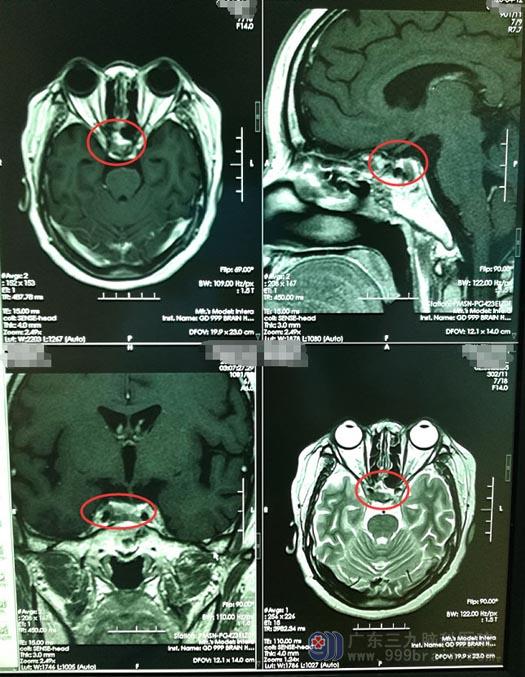

2018年,经朋友建议,小珍和家人来到了广东三九脑科医院神经外五科。头部MR检查提示:垂体底部病灶,待排垂体腺瘤;皮质醇 247.5 ↑ ug/L 、促肾上腺皮质激素 132.8 ↑ ng/L 。行内镜经鼻蝶垂体腺瘤切除术,手术顺利。术后复查内分泌结果:皮质醇 123.9 ug/L ,促肾上腺皮质激素 30.4 ng/L 。病理结果提示:多激素垂体腺瘤。

2个月前,小珍感到脸部痤疮又明显了。根据之前的经验,家人建议她赶紧回医院复查,颅脑MR显示“鞍区术区偏右侧占位性病变,半包绕右侧颈内动脉,考虑肿瘤复发”。小珍再次入住神经外五科。

▲手术前